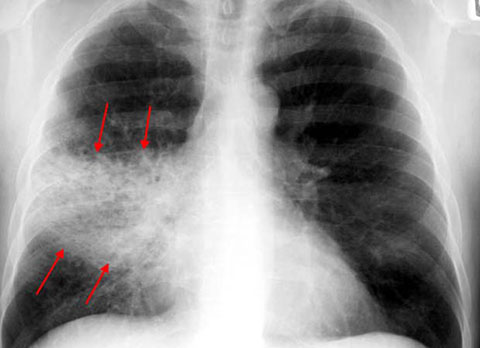

Типы поражения легочной ткани при пневмонии

При любом виде пневмонии степень поражения легких неодинакова, и от этого зависит насколько выраженными будут симптомы заболевания. По локализации и силе повреждения легочной ткани, можно классифицировать несколько типов воспаления. Чаще всего встречается очаговая пневмония, при которой поражается небольшой участок легкого, ей характерны такие симптомы, как мокрый кашель, температура и повышенная потливость. При тотальном воспалении поражается целиком одно из легких, а двустороннее охватывает оба органа одновременно,

- Рентгенография или флюорография грудной клетки.